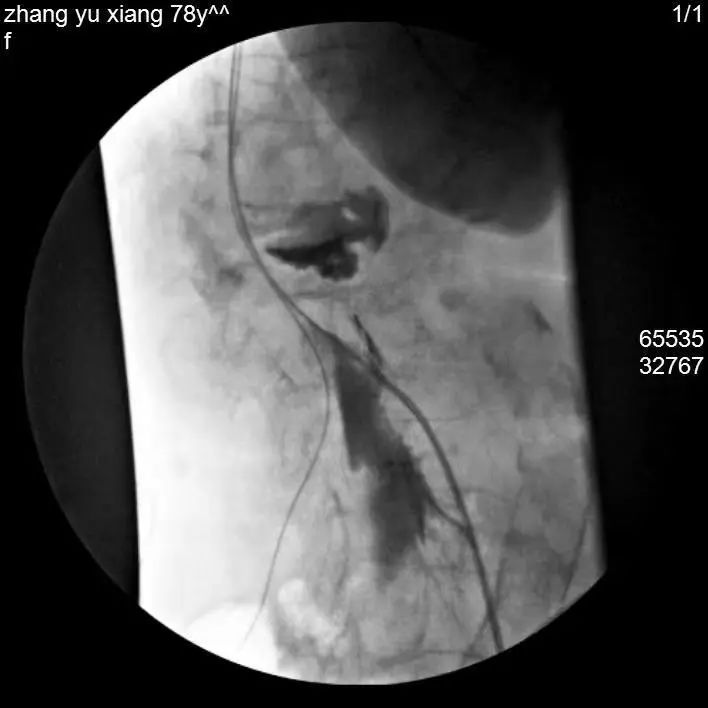

植入后电极及神经刺激器位置

术后,又联合内分泌及烧伤整形科进行血糖控制及创面管理,经过一个月的努力,张阿姨下肢皮肤温度较前回升,左足创面呈逐渐愈合趋势。